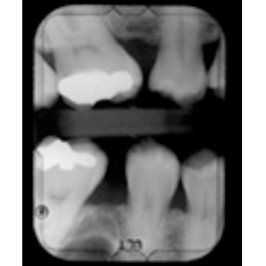

¿Y LOS RAYOS X?

En ocasiones, será necesaria una radiografía para poder hacer el tratamiento. De acuerdo con el Colegio de Radiólogos Americano, una sola RX no tiene dosificación suficiente para dañar al embrión o al feto. Utiliza siempre el mandil protector.